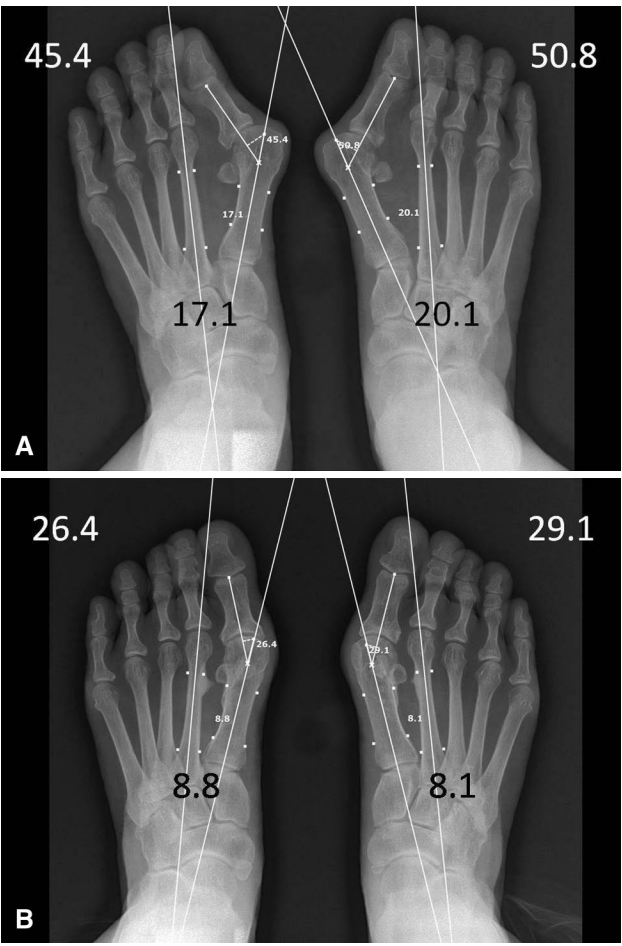

▲图示(A)75 岁女性患者术前站立位 X 线片示:双足畸形严重;双足美国足踝外科协会(AOFAS)拇趾评分均为 60 分;双足足趾跖趾关节角分别为 45.4° 和 50.8°,跖骨间角分别为 17.1° 和 20.1°。(B)术后 2 年站立位 X 线片示:第一跖骨内翻矫正效果满意,但因拇短屈肌外侧头可能存在挛缩,残留轻度拇外翻畸形;患者远端跖骨关节角轻度增大;右足 AOFAS 拇趾评分为 83 分,左足为 93 分。

▲图示(A)54 岁女性患者术前站立位 X 线片示:双足存在典型且无合并症的第一序列三联畸形,即拇外翻、第一跖骨内翻及跖籽分离,畸形程度为中度;术前美国足踝外科协会(AOFAS)拇趾评分为双足均 70 分。(B)术后 3 年站立位 X 线片示:拇趾、第一跖骨及籽骨复位满意,双足 AOFAS 拇趾评分均达 100 分。